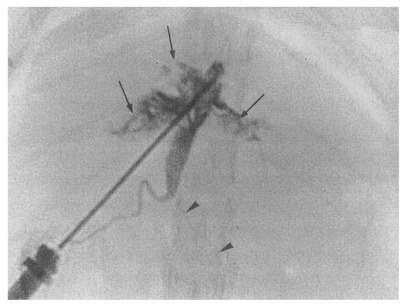

Cholangiographic findings

Cholangiography could not be performed in the normal control group because the bile ducts were too fine to puncture with a 26-gauge needle (Fig. 1). Cholangiograms showed moderate or marked dilatation of the bile duct confluence and of the proximal extrahepatic bile duct in the primary infection control group, the secondary infection control group, the reinfection I group, the reinfection II group, and the infection following immunization group. By contrast, the distal extrahepatic bile duct had a normal or near normal caliber (Fig. 8). In the primary and secondary infection control groups, and the infection following immunization group, multiple irregular filling defects were demonstrated on cholangiograms, indicating worms or desquamated materials (Fig. 9). These filling defects were hardly seen in the reinfection I and II groups. In these groups, the degree of dilatation of the bile duct at 26 weeks after reinfection (33 or 28 weeks after treatment, respectively) was slightly milder than that at 6 weeks after reinfection (13 or 8 weeks after treatment, respectively).

Fig. 8

Cholangiogram of a rat in the secondary infection control group 6 weeks after C. sinensis infection, showing marked dilatation of the bile duct confluence and of the proximal extrahepatic bile duct (thick arrows). Note the normal caliber distal extrahepatic bile duct (thin arrows). Pancreatic duct (arrowheads).

Fig. 9

Cholangiogram of a rat in the primary infection control group 4 weeks after infection, showing moderate dilatation of the bile duct confluence and of the proximal extrahepatic bile duct. A normally appearing distal extrahepatic bile duct is also shown. Note the multiple irregular filling representing worms or desquamated material (arrows). Pancreatic duct (arrowheads).